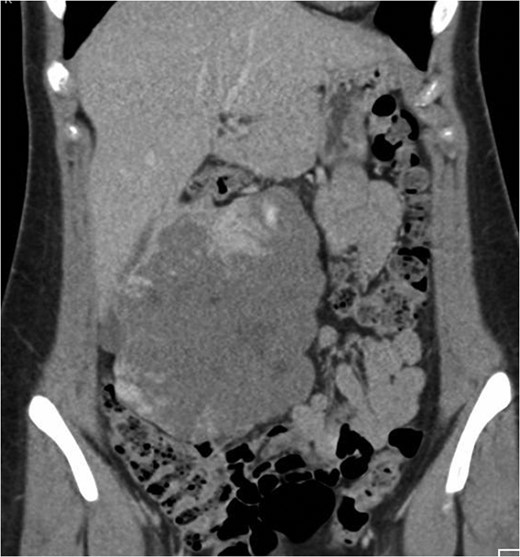

Coronal CT image in the portal venous phase demonstrating the large exophytic haemangioma.